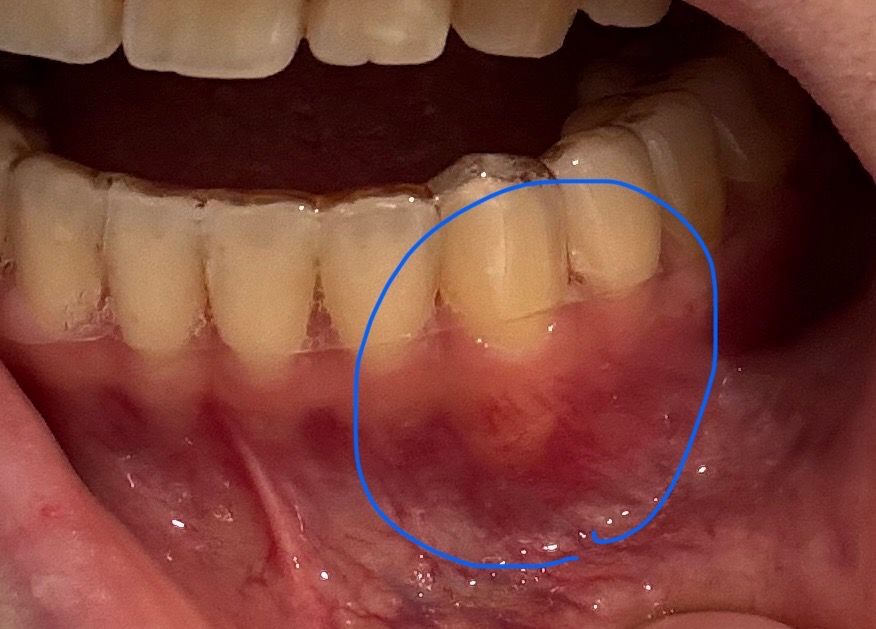

6개월이 지난 지금도 가끔 송곳니 뿌리에 통증이 있고 뿌리가 앞으로 뽑혀져 나와있는데요. 이거 안에 피 고인건가요? 여기만 빨간피가 뭉쳐있는 느낌인데.. 교정기를 한달전에 뗏고 여기 뿌리가 아직도 아픈게 잘못된거죠?

염증으로 보이시나요? 이거 신경 잘못되거나 아님 치아 뽑게되는걸까봐 걱정됩니다. 뿌리 이렇게 튀어나와도 괜찮은건가요? 이건 어떻게 치료받아야하나요?

• 1번 째 사진

치아가 이동하면서 위치상변화로 잇몸뼈가 얇은곳으로 이동해서 보이는 현상인거 같습니다. 염증이 잇거나 그래 보이진 않습니다.

교정을 하는 도중에 치아에 과도한 힘이 가해지게 되면 특정 치아의 뿌리가 노출되는 경우가 있습니다. 이런 경우 해당 치아에 신경이 감염이 되거나 생활력이 줄어들게 되면서 불편감이 느껴질 수 있습니다

이런 경우 신경치료가 필요할 수도 있습니다.

뿌리가 튀어나왔다기보다는 잇몸뼈가 잇몸이 얇아 비쳐보이는 겁니다 그 자체로는 큰 문제는 없으나 통증이 있다면 치과가보세요